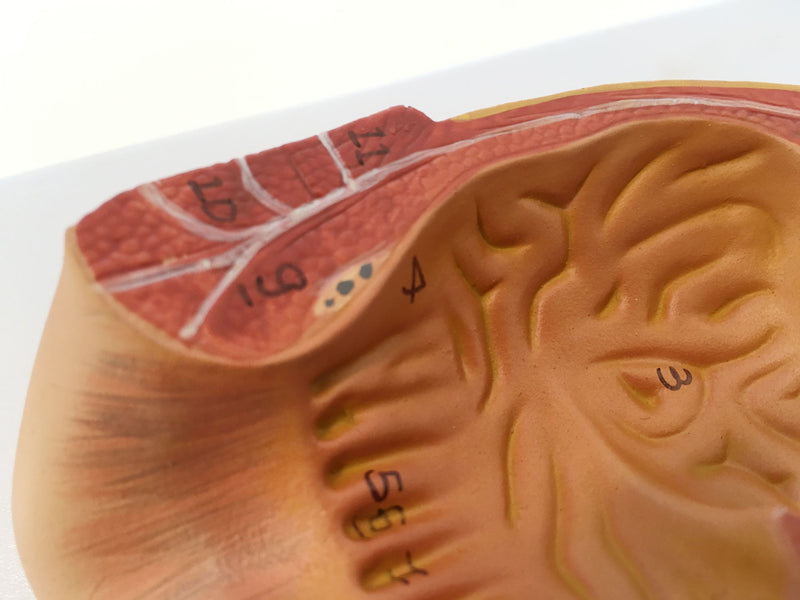

Rectum Cross-Section Model, 3X Enlarged

This model, three times life size, shows a frontal section of the human anus. The structures of the rectum, including the internal and external sphincter muscles, mucous membrane, ampullae, and anal valves are readily visible. Important anatomical structures are numbered; Accompanying an interactive 3D anatomical model with augmented reality is a great tool to encourage learning and support. This platform allows students to engage in comparative analysis of anatomical models as they compare and contrast the structure of individual organs. This initiative also provides a platform for continuing education, providing opportunities for all students to increase their knowledge of anatomy, physiology and pathophysiology.

Rectum Cross-Section Model, 3X Enlarged

This model, three times life size, shows a frontal section of the human anus. The structures of the rectum, including the internal and external sphincter muscles, mucous membrane, ampullae, and anal valves are readily visible. Important anatomical structures are numbered; Accompanying an interactive 3D anatomical model with augmented reality is a great tool to encourage learning and support. This platform allows students to engage in comparative analysis of anatomical models as they compare and contrast the structure of individual organs. This initiative also provides a platform for continuing education, providing opportunities for all students to increase their knowledge of anatomy, physiology and pathophysiology.